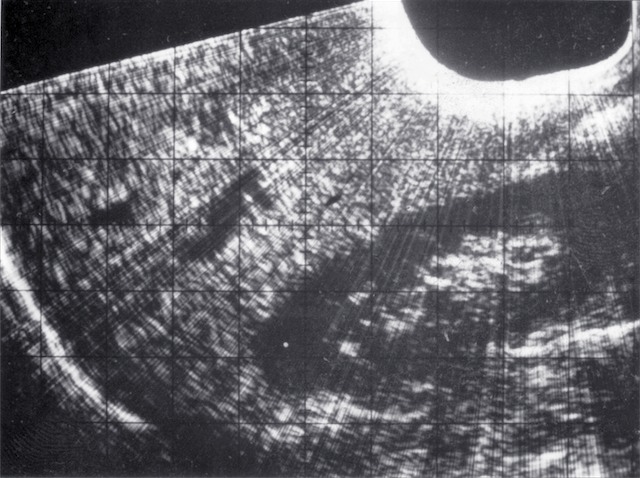

| 1993 | Development of real-time quasi-3D obstetric ultrasound |